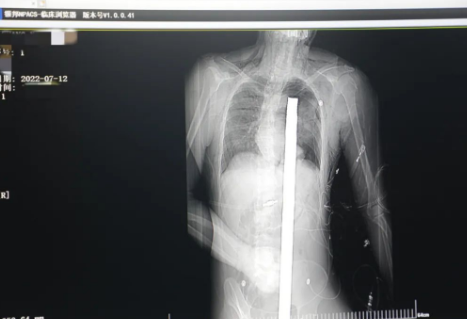

突發(fā)!太疼了,1.2米長的螺紋鋼從男子會陰部垂直穿入胸腔......7月12日下午16時10分,西安一處工地的一名26歲工友,不慎從10多米的高空墜落,不幸的是工地上一根直徑3厘米的螺紋鋼從男子會陰部垂直穿入體內,工地上的工友們小心翼翼地將連著的鋼筋截斷。情況危急,立即送往西安國際醫(yī)學中心醫(yī)院急救中心,此時正是下午17時00分。

時間就是生命!此時,西安國際醫(yī)學中心醫(yī)院展開了一場與生命賽跑的搶救,第一時間開辟綠色通道,急診X光片及CT顯示:異物經會陰部貫穿盆腔、腹腔到達左側胸腔主動脈弓水平。醫(yī)院創(chuàng)傷中心立即啟動應急預案,劉延彤副院長親臨指揮,下午17點48分,當患者被送達手術室,胸外、心外、肝膽外科、胃腸外科,泌尿外科及麻醉科等多學科專家聯(lián)手對這名工友進行“縱劈胸骨 前外側開胸探查 氣管及主支氣管修補 肺修補 血胸清除 開腹探查止血 腹膜后及盆腔探查......”手術。

情況緊急!術中探查后發(fā)現(xiàn),長120cm直徑3cm的螺紋鋼經患者右側會陰部穿入,傷及直腸,途徑膀胱后方,左側髂總動靜脈之間傷及左腎后,經胰腺后方在肝脾之間穿破膈肌,在下肺靜脈前方穿入左肺穿破氣管及左右主支氣管膜部,止于主動脈弓下水平,穿入體內的部分達到75cm。